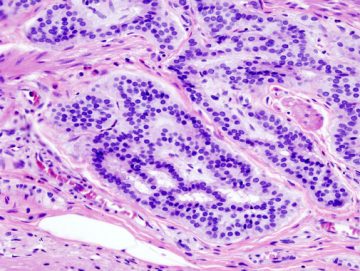

“Antes de aplicar una terapia basada en anticuerpos monoclonales, es preciso determinar si ciertos genes están mutados o no, porque esto nos indica si el tumor será resistente o sensible al tratamiento”, comenta. A día de hoy, los oncólogos ya saben que cuando los genes KRAS y NRAS sufren mutaciones, la terapia no tiene efecto. No obstante, en esta ocasión en el análisis genético de los 87 pacientes participantes se incluyeron estos y otros dos genes, TP53 y BRAF, y el resultado ha sido especialmente significativo en el caso del segundo.

Sin embargo, la investigación no se limita a señalar la importancia de este biomarcador. Los expertos han elaborado un método de puntuación que combina dos parámetros. El primero de ellos es el sistema de estadificación del cáncer colorrectal, que considera el grado de infiltración del tumor en la pared del intestino y su diseminación en tejidos cercanos, ganglios linfáticos y metástasis en otros órganos. El segundo incorpora la información sobre la presencia o ausencia de mutaciones sobre el gen BRAF.

Al combinar los dos parámetros anteriores se perfilan tres grupos de pacientes: los que tienen un 95% de posibilidades de recaer en dos años, los que presentan una probabilidad cercana al 50% y los que no van a recaer. Los casos que presentan estadios avanzados al diagnóstico y mutaciones en el gen BRAF constituyen el grupo de peor pronóstico, pero “su identificación precoz permitiría llevar a cabo un seguimiento más estrecho y anticiparnos a su eventual recaída”, destaca Sayagués.